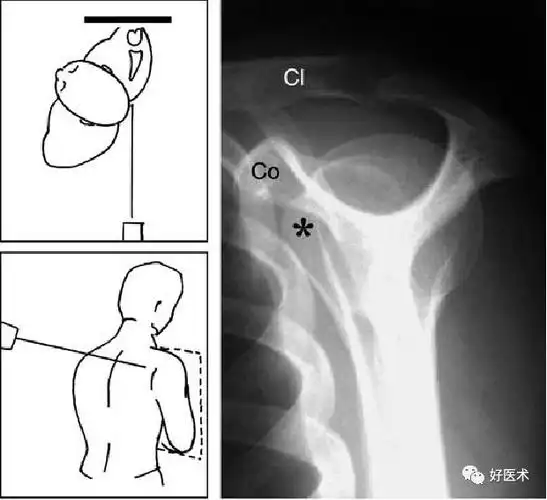

肩关节穿胸位图片

肩关节x线检查特殊体位